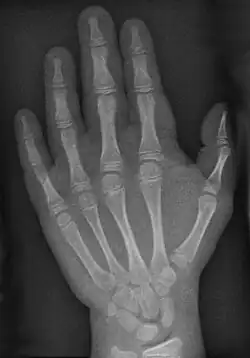

- Pencil-in-cup-Zeichen: („Bleistift in der Tasse“) Eine für die Arthritis psoriatica typische Deformierung der Fingergelenke.